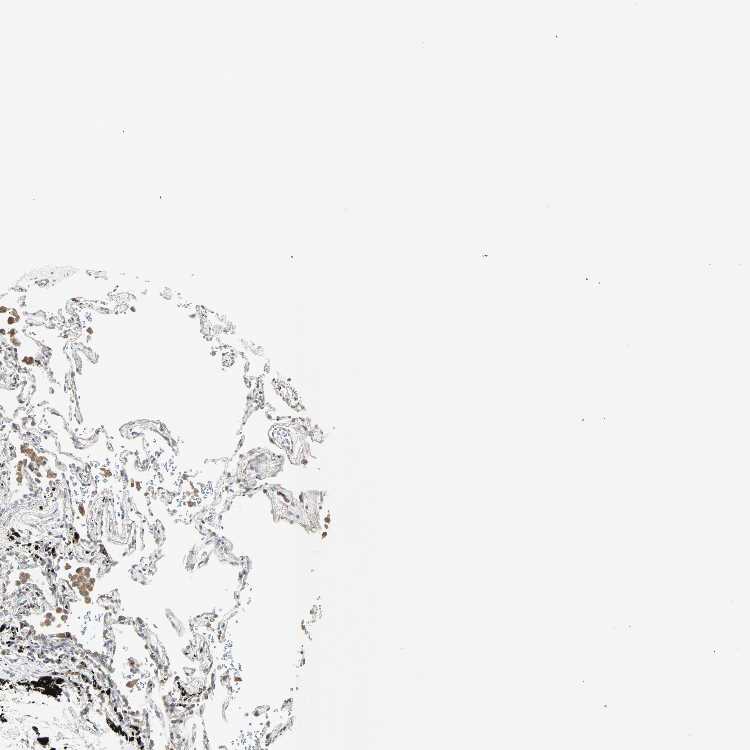

SOFT TISSUE 1 - Antibody stainingi

Antibody staining in the annotated cell types in the current human tissue is reported as not detected, low, medium, or high, based on conventional immunohistochemistry profiling in selected tissues. This score is based on the combination of the staining intensity and fraction of stained cells.

Each image is clickable and will lead to virtual microscopy that enables deeper exploration of all samples and also displays staining intensity scores, fraction scores and subcellular localization as well as patient and tissue information for each sample.

Antibody HPA007610

Fibroblasts Low

Peripheral nerve Not detected